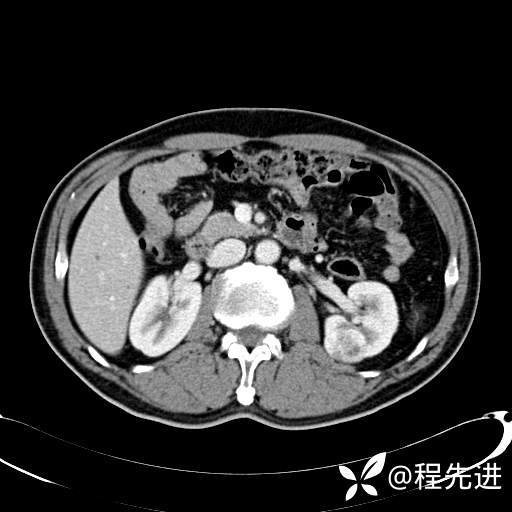

患者性别:男

患者年龄:65岁

简要病史:腰痛2月,体检发现左肾占位5天

平扫: